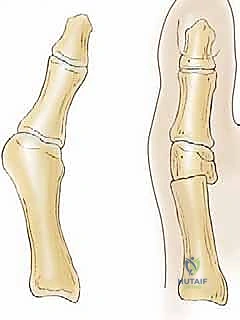

- الابتعاد عن صفائح النمو: تُجرى هذه الجراحة في الجزء القاصي (البعيد) من عظم المشط الأول، بالقرب من المفصل، بعيداً تماماً عن صفيحة النمو الرئيسية الموجودة في قاعدة العظم. هذا يضمن عدم إعاقة نمو قدم المراهق.

- تصحيح ثلاثي الأبعاد: تسمح جراحة ميشيل بإزاحة رأس عظم المشط نحو الخارج (لتصحيح الانحراف)، وإلى الأسفل قليلاً (Plantarflexion) لمنع حدوث ألم في الأمشاط الأخرى مستقبلاً.

- الاستقرار الهيكلي: التعديلات الحديثة التي يطبقها الدكتور هطيف تجعل العظم المقطوع متداخلاً (Step-cut)، مما يوفر استقراراً ممتازاً ويسرع من عملية الالتئام.